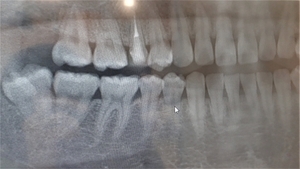

少し見えて横になった親知らず

親知らずのレントゲン

親知らずの歯はどこの場所?

親知らずは、永久歯(大人の歯)の中で最後に発育する歯で、中切歯(最前方の前歯)から数えて8番目の最後方歯に位置しています。

18歳前後から生えてくるので、20代前半までに抜歯するのがおすすめです。

親知らずは必ずしも抜かなければいけないものではありませんが、痛みや腫れを繰り返す場合や、他の歯に影響を及ぼしてしまう可能性がある場合は抜歯を行う必要があります。

親知らずの抜歯は、時間がかかる?

親知らずの抜歯は、親知らずの状態によって30分~1時間半程度で終了します。簡単な場合は普通の歯を抜くのと同様にすぐ抜けますが、歯の大部分が骨の中に埋まっていたり、歯と骨が癒着していたり、歯の根の形が複雑だったりすると抜くのにもかなりの時間がかかります。親知らずは、何歳の時に抜くべきか?

親知らずは18歳前後から生えてくるので、20代前半までに抜歯するのがおすすめです。年齢を重ねるにつれて歯は硬くなるため、親知らずを抜くタイミングが遅くなるほど抜歯に時間がかかるようになります。